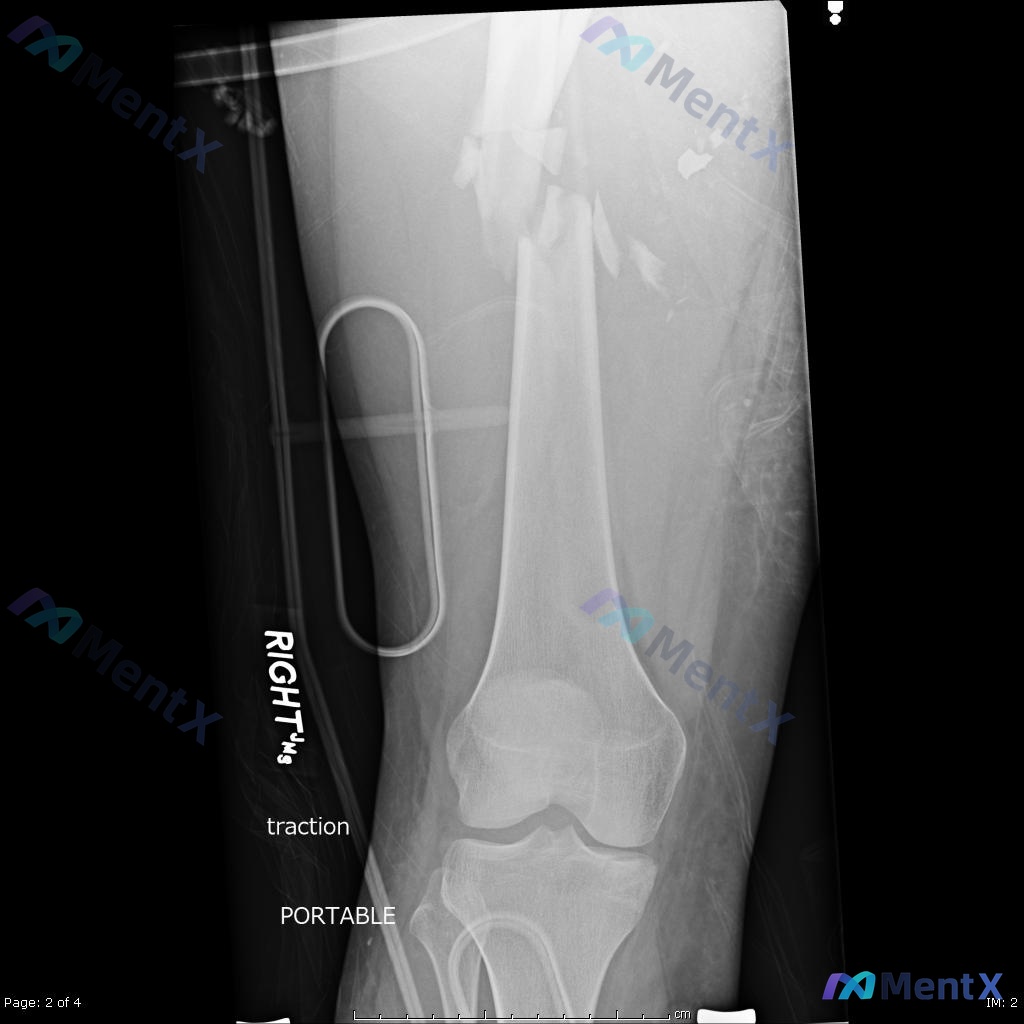

看到一个挺有代表性的创伤骨科病例,结合影像和临床分析整理了一下思路,关于「髓内钉固定术后负重时机」的误区其实还挺普遍的。 --- 一、先把病例核心信息捋清楚 基本情况:22岁男性,高能量车祸受伤 影像关键所见: - 术前(图A/B):右侧股骨干中段粉碎性骨折,多块游离骨块,移位明显;局部软组织肿胀;...